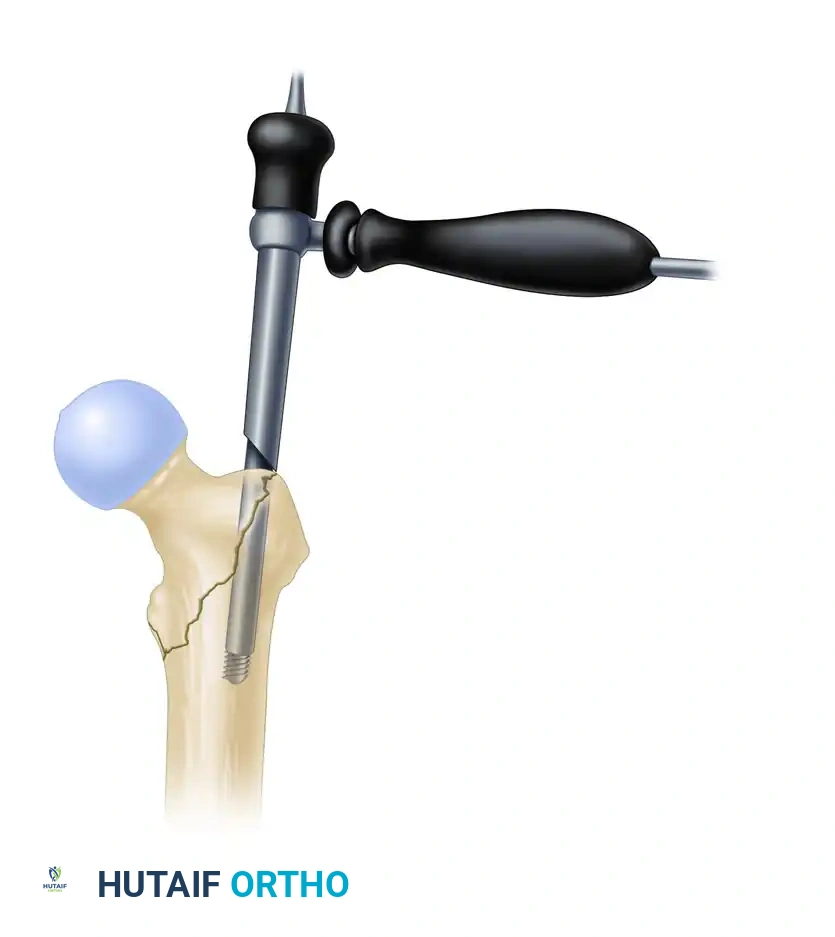

Insertion of the entry reamer/channel reamer combination to the level of the lesser trochanter.

- Introduce the 12.5-mm entry reamer / 16-mm channel reamer combination through the soft tissue guide (entry portal tube) over the guide pin.

- Insert the channel reamer to the level of the lesser trochanter. The entry portal tube features a positive stop to prevent over-insertion.

- For a long InterTAN nail, remove the entry reamer and guide pin at this time, leaving the channel reamer in place to protect the proximal soft tissues and guide subsequent instrumentation.